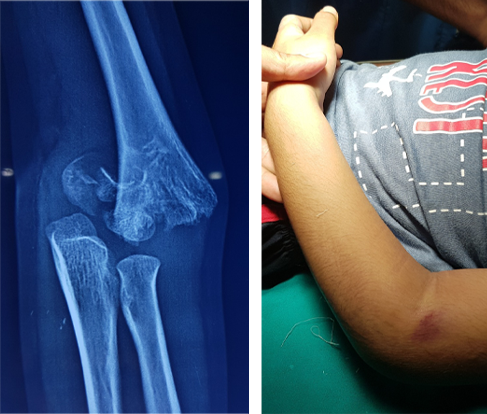

Case - 1

Elbow Fracture

Before

Swelling, Pain, Bruises and inability to move the elbow

After

Treatment may vary from as simple as sling application to an urgent surgery depending upon the severity of fracture

Full extension & full flexion of both the elbows